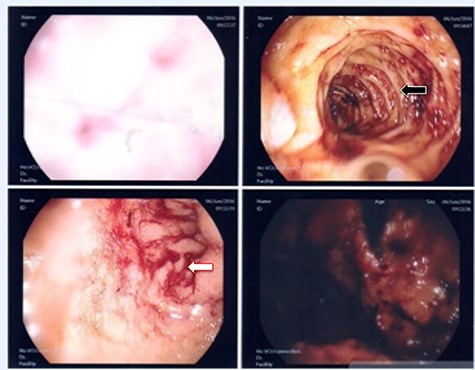

A 36-year-old obese female patient underwent a sleeve gastrectomy abroad. Eleven days after surgery, she presented with an abdominal pain. Abdominal computer tomography (CT) revealed several fluid-air collections (3 abscesses) around the upper greater gastric curve (3.5 × 3.2 cm), lesser sac (7 × 3.3 cm) as well as anterior to the spleen (7 × 3.3 cm). By that time, there was also left pleural effusion and atelectasis of the left lower lung lobe. On the next day, CT-guided aspiration was done (Fig. 1) and a pigtail catheter was inserted to drain the abscesses. On the following day, water-soluble oral contrast displayed an active contrast leak along the proximal sleeve gastrectomy (Fig. 2). On the same day, covered esophageal stent was placed endoscopically. The patient was discharged home and was scheduled for stent removal after 2 weeks. However, after 2 days, the patient presented again with an abdominal pain. The plain x-ray showed slippage of the stent distally. Upper GI endoscopy was done, and the esophageal stent was removed. One day later, the patient condition deteriorated with a massive upper GI bleeding. A CT angiography showed no extravasation and the source of bleeding was not identified during endoscopy due to massive bleeding. An immediately performed angiogram revealed an AEF (Fig. 3). The interventional radiologist achieved transient cessation of the bleeding through embolization of the fistula with interlock coils (Fig. 3). An aortogram showed continuous extravasation of contrast through the fistula, and therefore, endovascular intervention was performed with implantation of 22 mm × 112 mm aortic stent (TEVAR using Valiant covered stent - Medtronic company, USA). One week after TEVAR, another long esophageal stent was positioned (from lower esophagus to the stomach). Two weeks later, a barium swallow proved no evidence of contrast leak. Then, the esophageal stent was removed, and the patient was discharged home. There was a plan for definitive reconstruction procedure, including removal of the endovascular stent and use of reconstructed pericardial bovine graft, however, the patient declined. About 10 months later, she presented with another attack of massive hematemesis, with a drop of hemoglobin to 8 g/dl and a blood pressure of 66/44 mmHg requiring a rapid sequence induction and infusion of packed red blood cells. An immediate abdominal CT showed evidence of peri-stent infection with no contrast extravasation. Upper GI endoscopy showed an evidence of an ischemic ulcer above the Z-line with granulation tissue at the ulcer edge and erosion of the endovascular stent into the lower esophagus. The patient had a positron emission tomography (PET) scan and diagnosed with mediastinitis due to aortic stent infection and septic shock (Fig. 4). Surgical intervention was offered but the patient declined. Treatment with broad spectrum antibiotics and blood transfusion were administrated as required. Around 5 weeks later, the patient developed massive upper GI bleeding requiring intubation and surgical intervention (distal esophagectomy with removal of the endovascular stent and resection and replacement of the AEF site with reconstructed tube using 14 × 9 cm bovine pericardial graft through left thoraco-abdominal incision utilizing left cardiopulmonary bypass and distal perfusion through left femoral artery (Fig. 5). Closure of the stomach with gastrostomy tube insertion for feeding had been performed. One and half year later, reconstruction surgery of the esophagus with colonic interposition was done. After 3-year follow-up, the patient was doing well with no complication.

(A) Aortography showed active contrast extravasation to the esophagus trough the fistula. (B) Coli embolization of the AEF with contrast beyond the coil. (C) Esophagogastroduodenoscopy revealed the site of the fistula and the coil embolization in the stomach. (D) An esophageal stent was placed extending to the stomach and the aortic stent in place. Feeding tube in place.

Esophagogastroduodenoscopy revealed thoracic endovascular aortic stent can be seen in the distal esophagus. (B) PET scan showing increase FDG activity around the distal aortic stent.